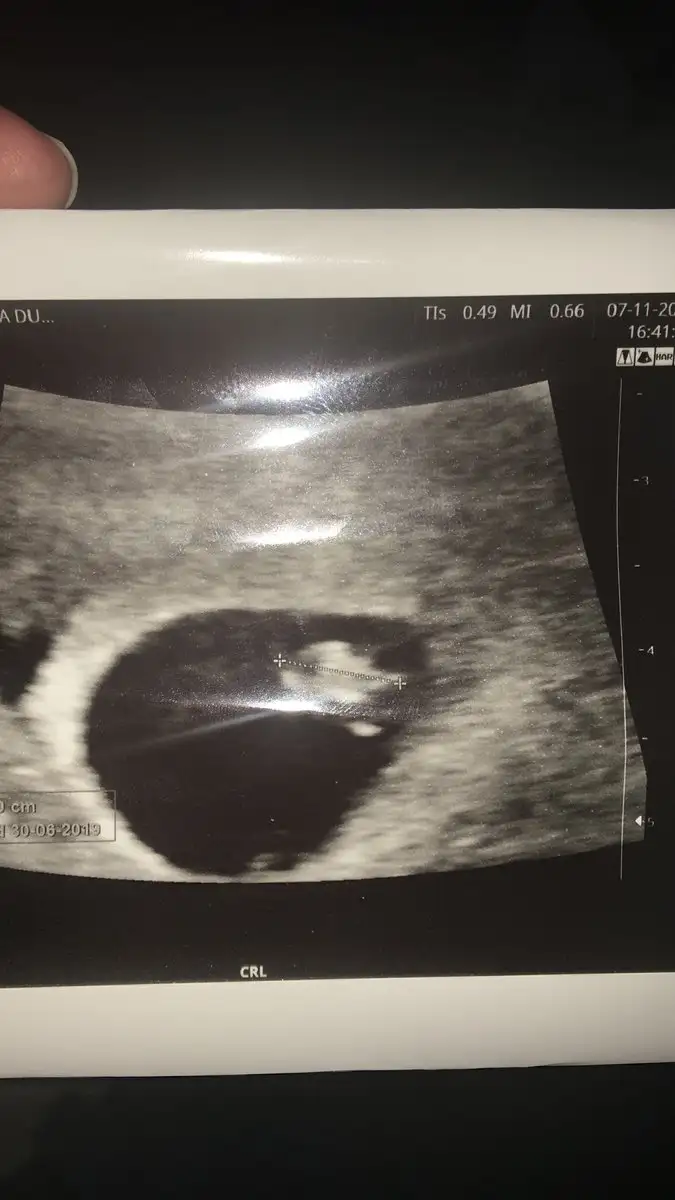

Ben de bugün bebeği gördüm ve kalp atışını duydum kızlar çok şükür bambaşka bir duyguymuş Allah isteyen herkese nasip etsin biz de yavrularımızı hayırlısıyla kucağımıza alalım inşallah. 0,7 cmmiş 6+3 ile uyumlu dedi ama 7+3tüm aslında inşallah sonradan yakalarız :anne: